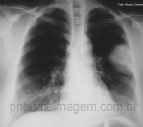

O PNEUMOIMAGEM ALCANÇA 2000 AMIGOS NO FACEBOOK

Alcançamos hoje o número de 2000 amigos no Facebook! Graças a vocês, hoje o PneumoImagem se constitui na maior comunidade em Pneumologia do Facebook no Brasil! O PneumoImagem surgiu há três anos como um site de imagens em Pneumologia, on...